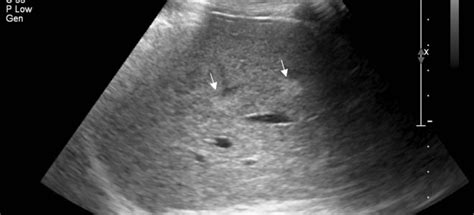

Размеры печени у взрослого и ребенка: норма, ме...

Размеры печени в норме и при заболеваниях | Все...